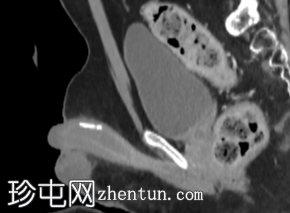

矢状位增强CT(门静脉期)

腹部和盆腔增强CT显示,沿白膜/阴茎海绵体周围走行可见钙化斑块。最大的斑块位于阴茎背侧,长度达19毫米。

佩罗尼氏病以白膜内形成纤维炎症性斑块为特征,这些斑块随后可能发生钙化/骨化。虽然诊断通常基于临床表现,并辅以阴茎超声检查,但CT扫描也可能偶然发现沿白膜/阴茎海绵体走行分布的线状/斑块状钙化。

本例中,因腹痛行CT检查时偶然发现阴茎背侧海绵体钙化斑块,其中最大斑块直径为19毫米,这是佩罗尼氏病钙化斑块的典型影像学表现。

CT扫描中阴茎钙化的鉴别诊断有限,可能包括既往外伤/炎症引起的营养不良性钙化、血栓形成血管钙化或罕见钙化病变;然而,斑块状的背侧海绵体分布最符合佩罗尼氏病。